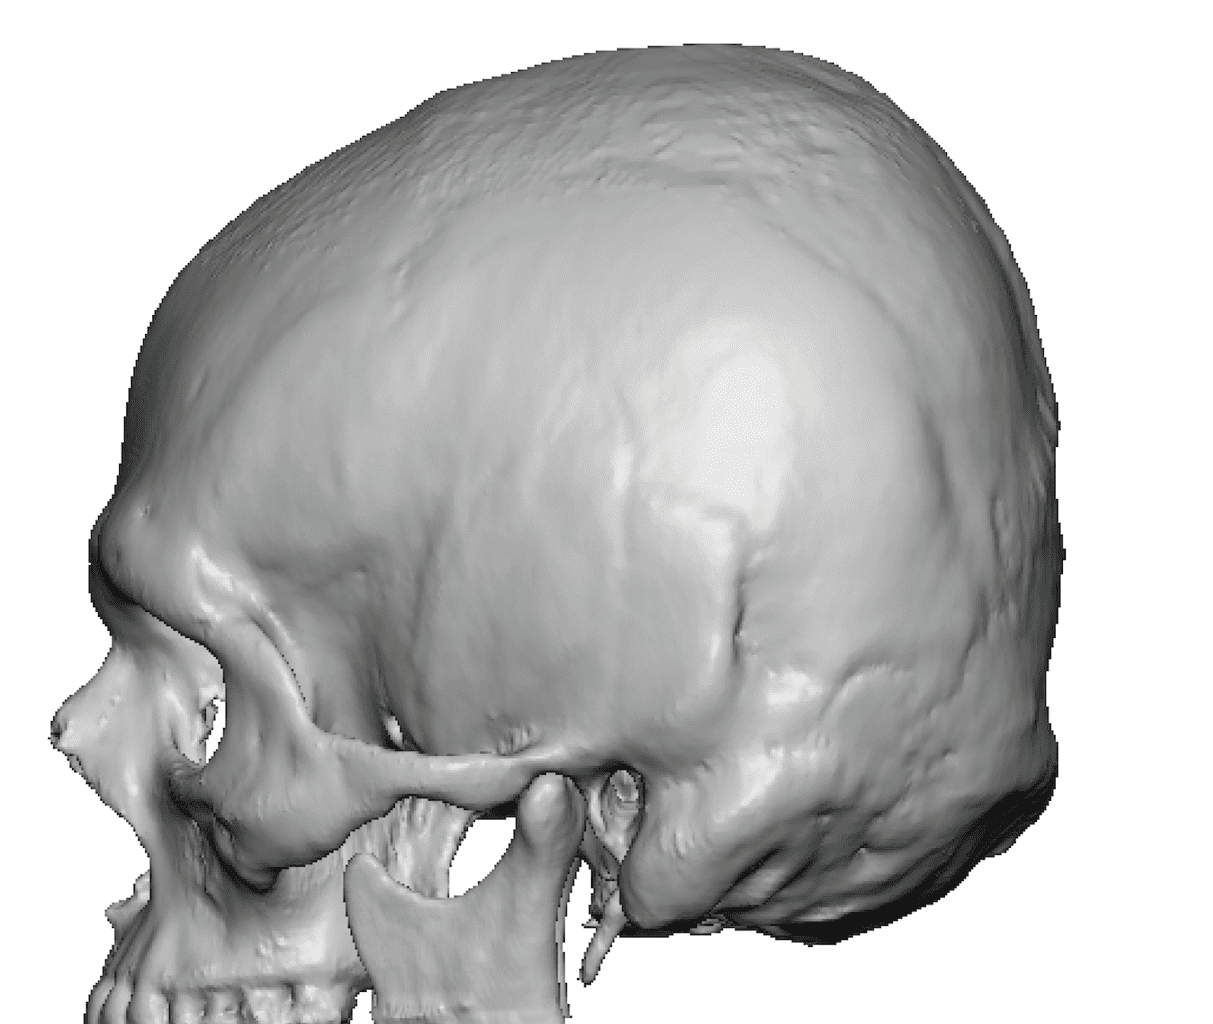

Patient 28

Desire for rounder shape to the top of the head from a congenital parasagittal deficiency skull shape.

Custom skull implant designed to fill in the parasagittal deficiencies.

Desire for rounder shape to the top of the head from a congenital parasagittal deficiency skull shape.

Custom skull implant designed to fill in the parasagittal deficiencies.